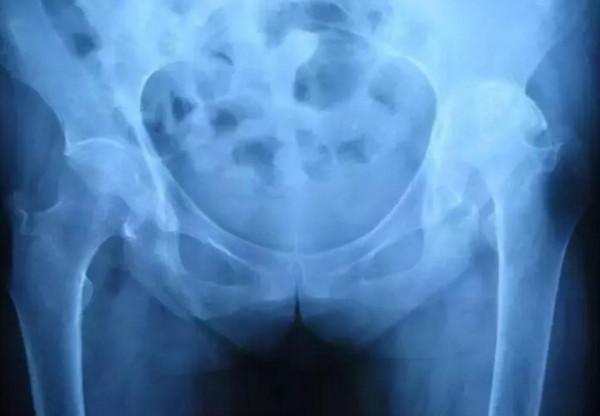

在人的髂骨和骶骨之間有一個關節叫骶髂關節,這是強直性脊柱炎最早出現症狀的部位,因此下腰疼痛是最常見的症狀。隨著疾病的進展,由骶髂關節向上擴散,逐漸向腰椎、頸椎、胸椎椎角炎。脊椎角部炎症基礎上的骨質增生,導致骨贅形成,脊柱逐漸僵硬,病人脊椎活動緩慢下降。由於出現僵硬等症狀,故稱強直性脊柱炎。

一項由美國細胞外科協會向美國FDA申請的381例PRP用於治療強直的病例,總有效率為81%,並不同程度地增加了軟骨組織。X片顯示大多數患者在治療6至12個月時關節間隙增厚。